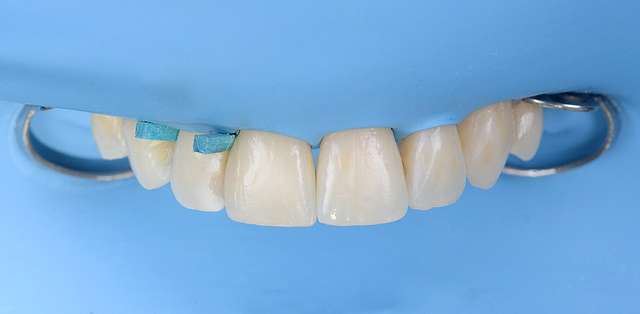

Here we had to deal with a significantly deviated midline, needed to bring one canine on the arch and basically realign teeth on both arches. To finish we did some composite details. When existing teeth have naturally beautiful shapes, orthodontics is many times a superior alternative to prosthetic treatment. It has one disadvantage: requires more time.